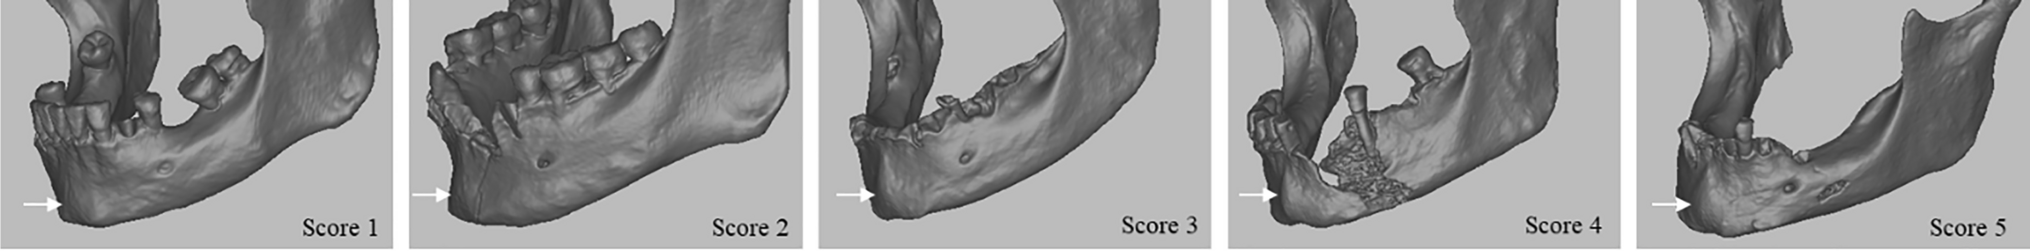

The method by Walker (2008) encompasses five traits (nuchal crest, mastoid process, supra-orbital margin, glabella, and mental eminence), scored according to an ordinal scale from 1 (female/gracile) to 5 (male/robust), with scores 2 and 4 corresponding to "probably female" and "probably male" morphologies, respectively, and score 3 to "indeterminate". We based our scoring on the criteria listed by Walker (2008) and MorphoPASSE [5]. Considering the finding by Braun et al. (2022), we will divide the mental eminence trait into the mental tubercles and the sagittal mental protuberance in our study, in addition to scoring the traditional mental eminence. With this attempt, we keep two features apart that make the human menton 'much more complex' in its expression [49] than the description in Walker [4] might suggest. To score the expression of the mental tubercles and the mental protuberance, we applied the same scoring protocol (scores 1 to 5), with minimal and maximal expression of the traits corresponding to score 1 and score 5, respectively (Figs. 1 and 2, Table 2).

Fig. 1

CT scans of mental tubercles (black arrows) scores 1 to 5 with increasing expression of the trait, independent from mental protuberance. Individuals Ins Kirchgemeindehaus (3465, 3466, 3469) and Twann (3365 and 3371), respectively

Fig. 2

CT scans of mental protuberance (white arrows) scores 1 to 5 with increasing expression of the trait, independent from mental tubercles. Individuals Ins Kirchgemeindehaus (3543, 3472, 3469, 3529) and Steffisburg (3975), respectively